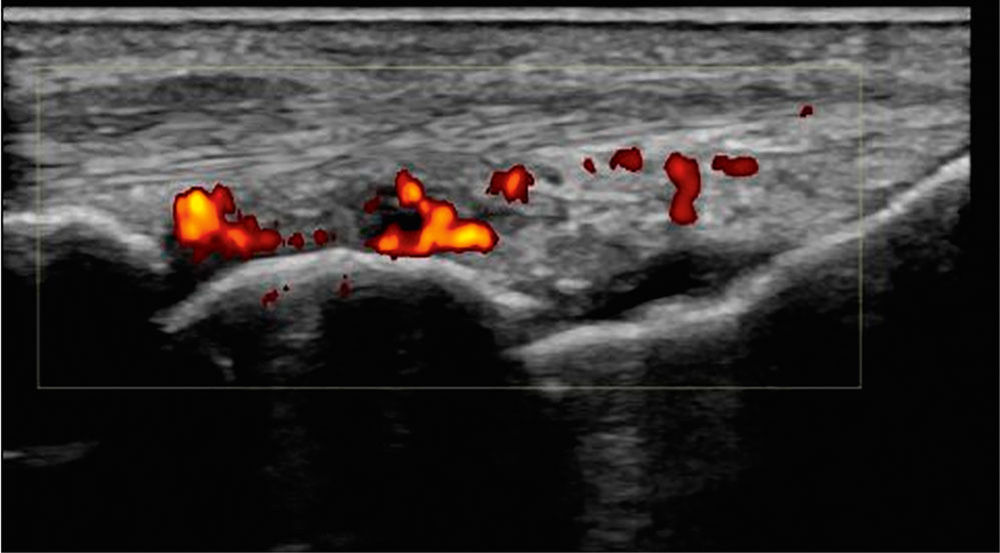

Ein 78-jähriger Patient stellt sich mit seit über acht Wochen bestehenden, symmetrischen Gelenkschwellungen der Hände vor. Die Beschwerden gehen mit ausgeprägten Schmerzen einher (numerische Ratingskala 7/10). Zusätzlich berichtet er über eine morgendliche Gelenksteifigkeit von etwa 90 Minuten, in dieser Zeit ist ein Faustschluss nicht möglich. Im Tagesverlauf bessern sich Schmerzen und Funktionseinschränkung unter zunehmender Mobilisierung. Die Entzündungsparameter sind erhöht (CRP 3,8 mg/dl [Norm < 0,5 mg/dl], BSG 72 mm/h). Autoimmunserologisch sind sowohl Rheumafaktor, als auch Anti-CCP-Antikörper positiv. Anamnestisch und klinisch ergeben sich keine Hinweise auf eine Infektion. Es imponieren deutlich geschwollene Handgelenke sowie MCP-Gelenke II bis IV beidseits. Arthrosonografisch zeigt sich an den betroffenen Gelenken eine floride Synovitis (Abbildung 1).

Abbildung 1: Ultraschallbefund eines Handgelenks im dorsalen Längsschnitt mit Power-Doppler-Positivität als Zeichen der Inflammation (farbliche Kodierung).